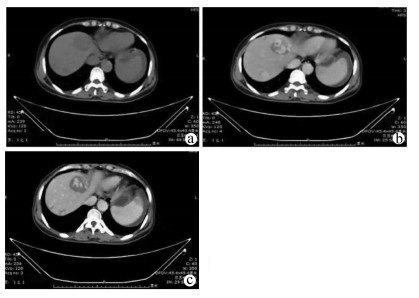

A case of acute cerebral infarction with splenic rupture secondary to splenic infarction

2021, 37(10): 2417-2419. DOI: 10.3969/j.issn.1001-5256.2021.10.033

Abstract(947) HTML (288) PDF (2433KB)(44)

Abstract: